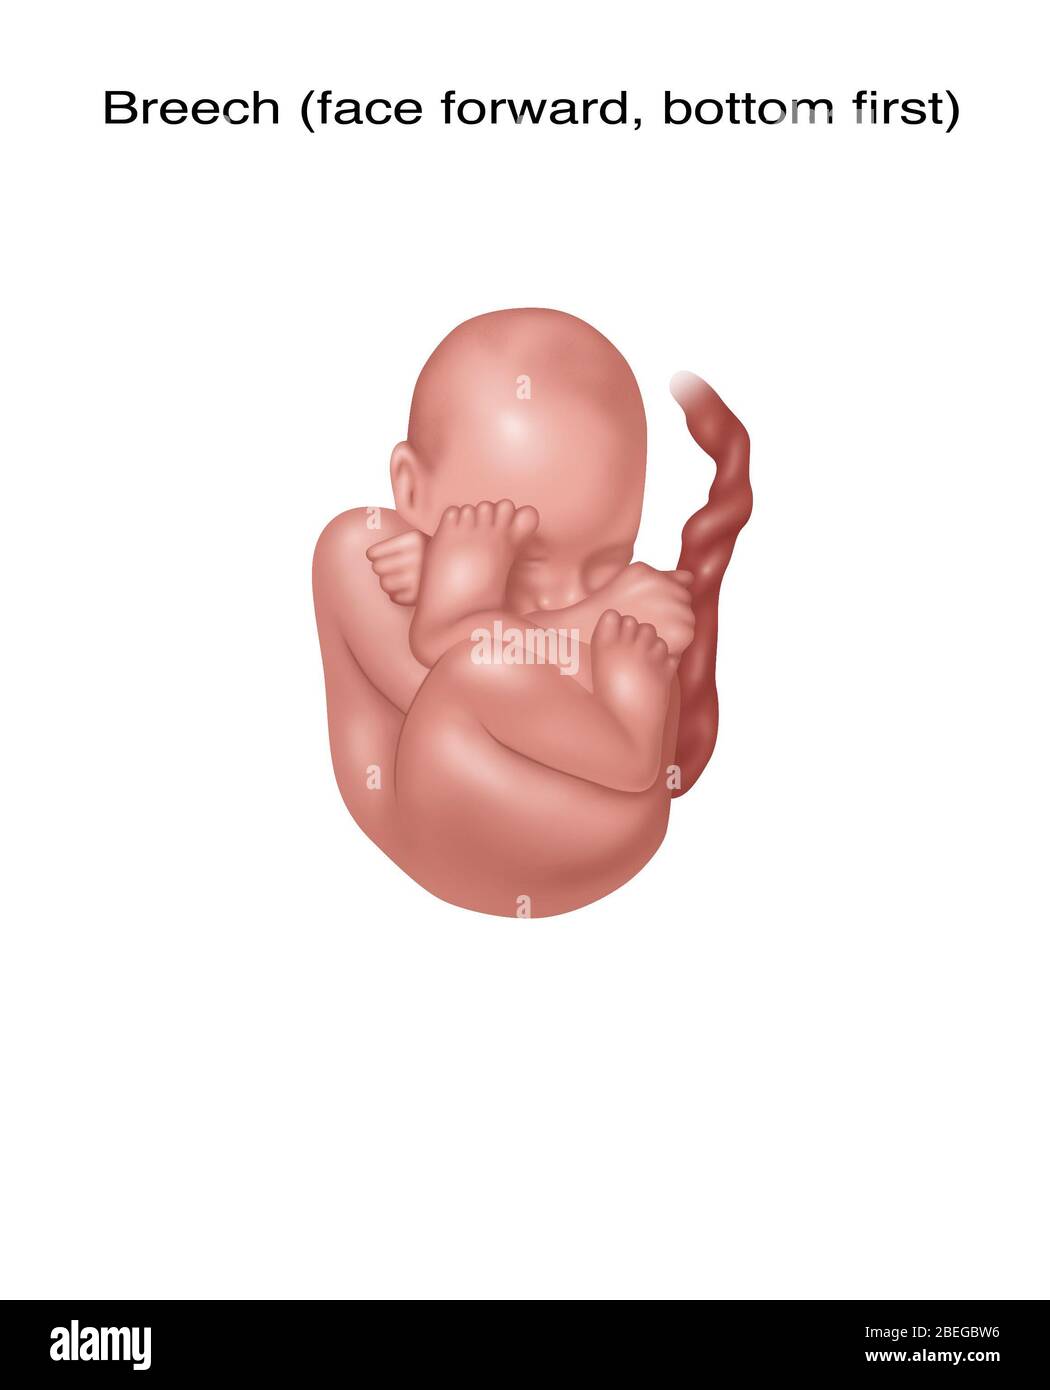

Fetus Positions in Uterus, Illustration Stock Photohttps://www.alamy.com/image-license-details/?v=1https://www.alamy.com/fetus-positions-in-uterus-illustration-image353173031.html

Fetus Positions in Uterus, Illustration Stock Photohttps://www.alamy.com/image-license-details/?v=1https://www.alamy.com/fetus-positions-in-uterus-illustration-image353173031.htmlRF2BEGBPF–Fetus Positions in Uterus, Illustration

Fetus Positions in Uterus, Illustration Stock Photohttps://www.alamy.com/image-license-details/?v=1https://www.alamy.com/fetus-positions-in-uterus-illustration-image353173074.html

Fetus Positions in Uterus, Illustration Stock Photohttps://www.alamy.com/image-license-details/?v=1https://www.alamy.com/fetus-positions-in-uterus-illustration-image353173074.htmlRF2BEGBT2–Fetus Positions in Uterus, Illustration